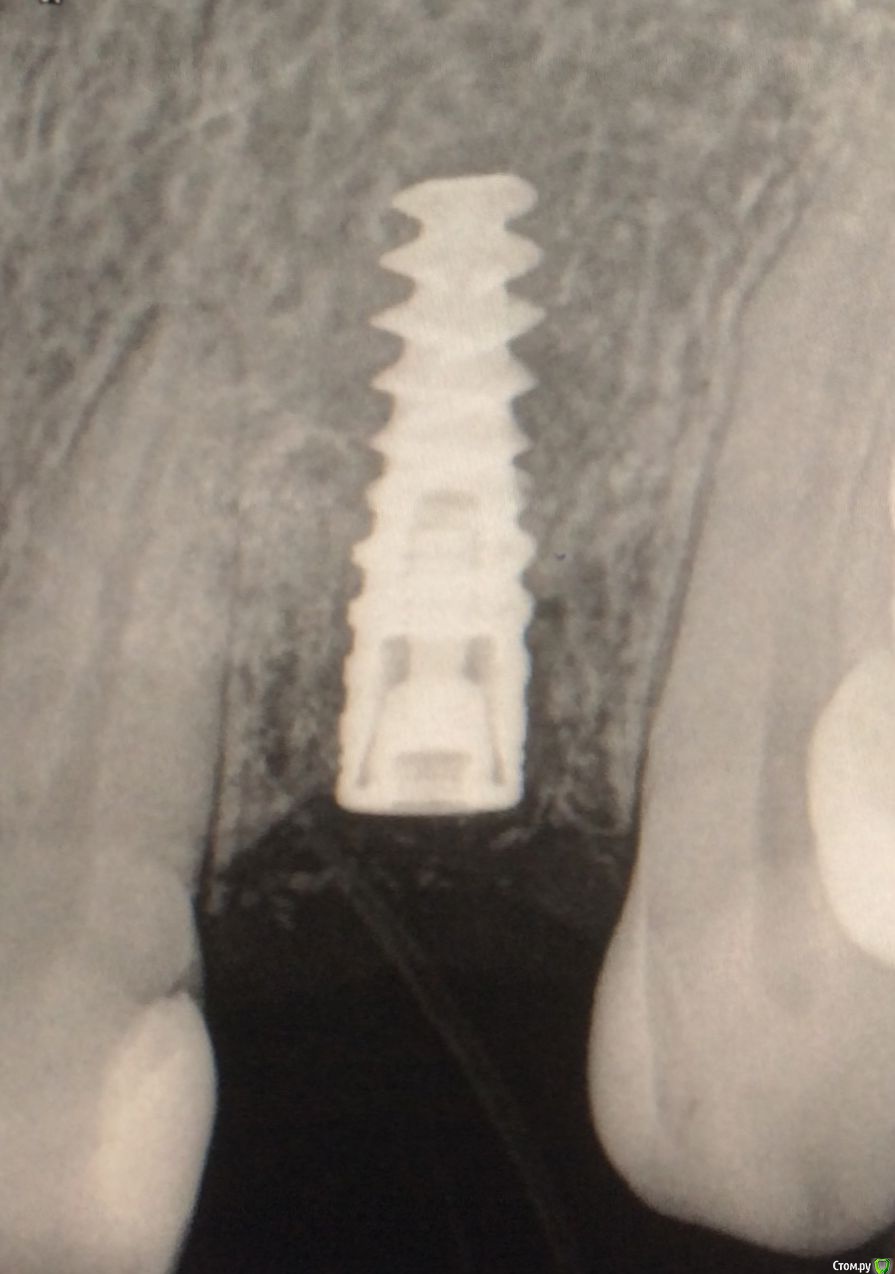

Kitty82 Опубликовано 15 сентября, 2015 Автор Поделиться Опубликовано 15 сентября, 2015 снимок на этапе установки формирователя десны. 4 недели назад Ссылка на комментарий